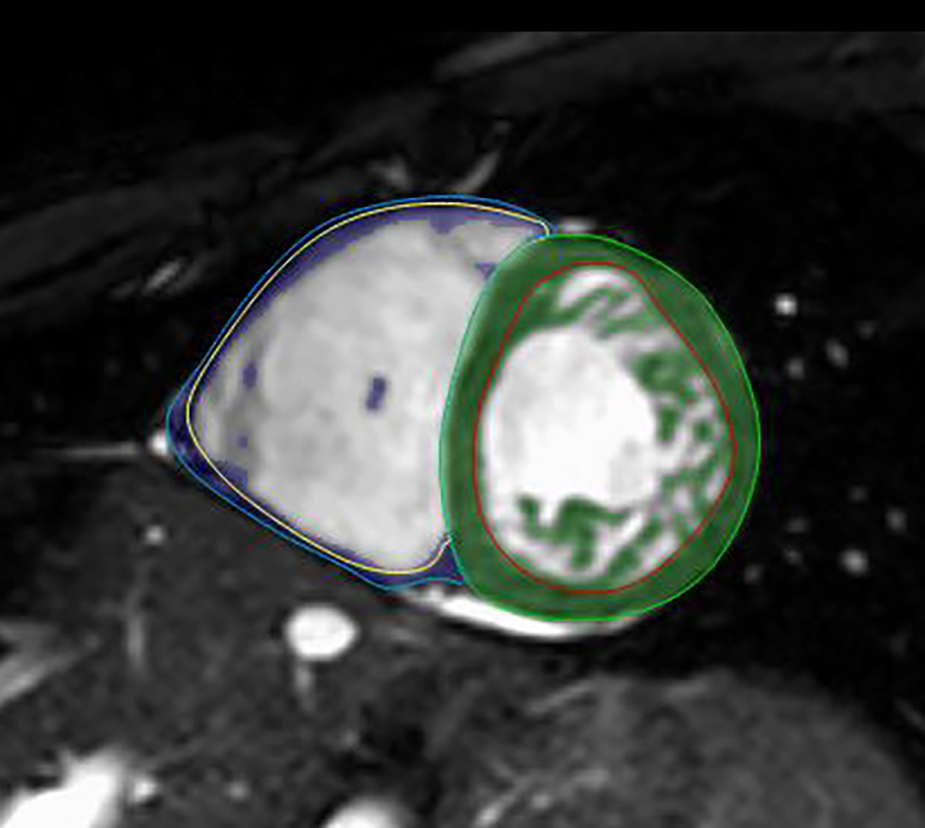

Semiautomatic tracing with manual correction from base to apex was used on end-diastolic and end-systolic SA cine images, and then the threshold-based (TB) algorithm (MassK module of the Medis Suite QMass program) was applied. Based on different signal intensities, the TB program classifies each voxel as blood or myocardium. The voxels identified as myocardium on the end-diastolic images within the epicardial contours represent the total myocardial mass (TM), and those within the endocardial border form the trabeculated and papillary muscle mass (TPM) (Figure 2). The threshold was set to the default of 50% (26). Manual correction of the threshold was not performed.

Figure 2

LVNC on short-axis CMR images with the threshold-based postprocessing method. Within the green (LV) and blue (RV) epicardial contours, the program identifies each voxel as blood or myocardium. The voxels identified as myocardium within the red (LV) and yellow (RV) endocardial borders represent the TPMi, which is green in the LV and purple in the RV. CMR, cardiac magnetic resonance imaging; LV, left ventricle; LVNC, left ventricular noncompaction; RV, right ventricle; TPMi, trabeculated and papillary muscle mass index.